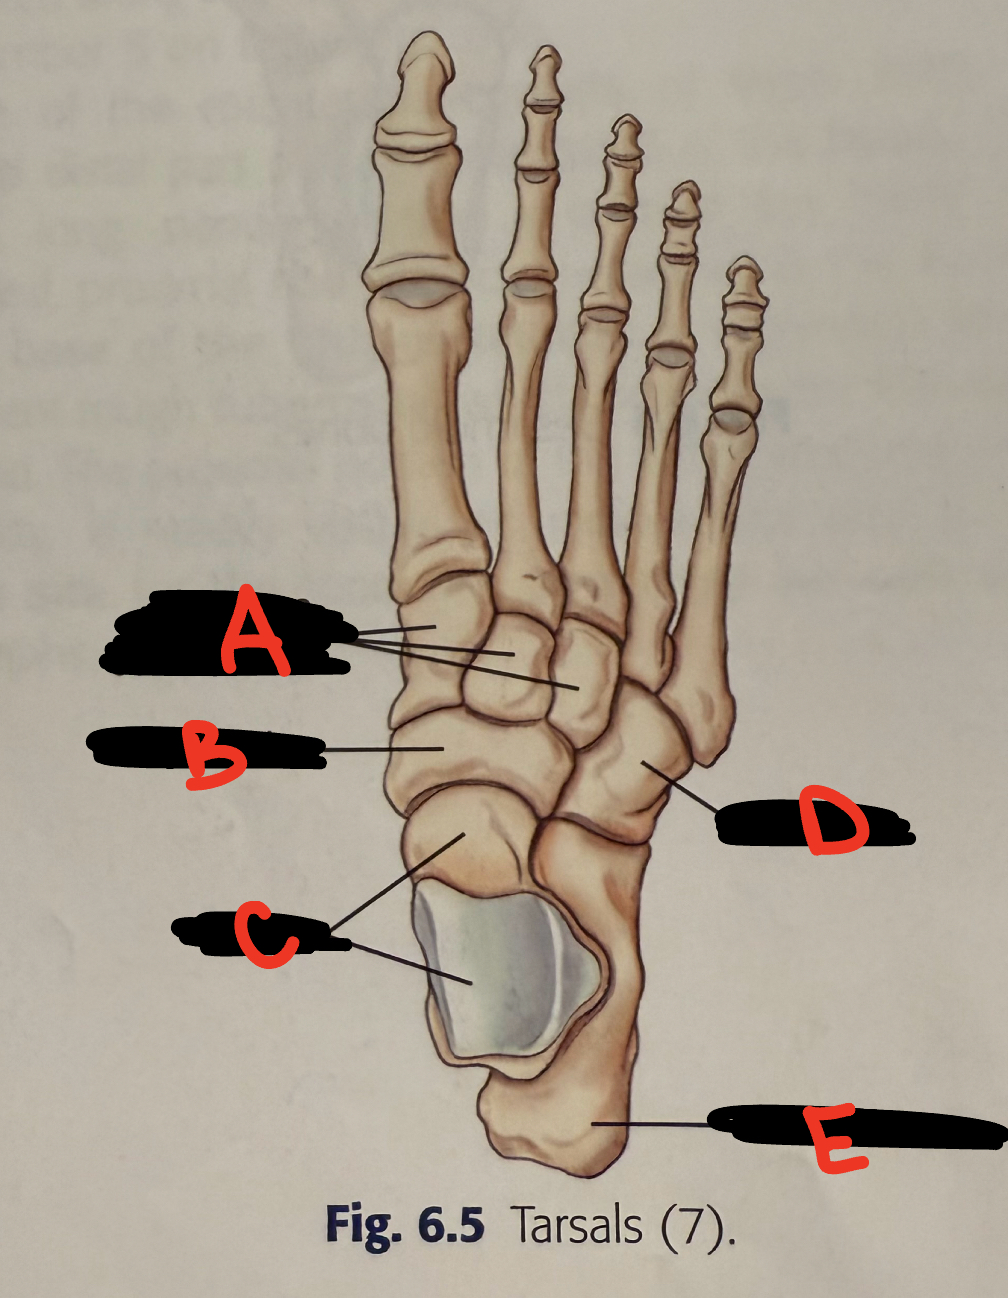

<p>A</p>

cuboid

<p>B</p>

3rd cuneiform

<p>C</p>

2nd cuneiform

<p>D</p>

1st cuneiform

<p>E</p>

transverse arch